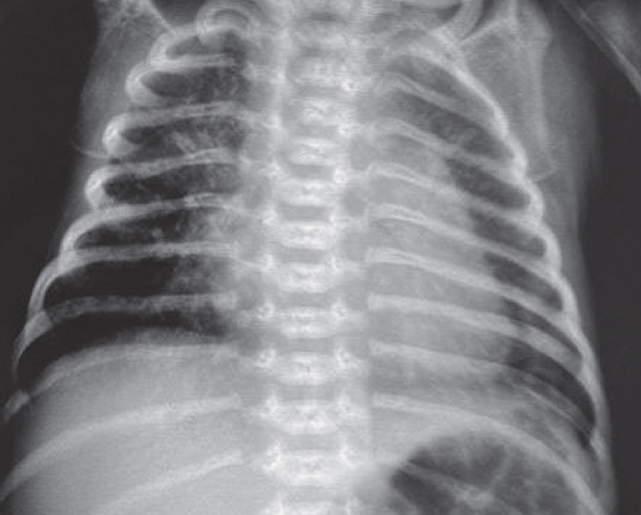

На контрольной рентгенограмме, выполненной на вторые сутки жизни (после введения сурфактанта), сохраняются признаки тяжелого РДС, осложнившегося правосторонним напряженным пневмотораксом (рис. 2), в связи с чем по экстренным показаниям было выполнено дренирование плевральной полости.

Рис. 2. Рентгенограмма органов грудной клетки новорожденного после введения сурфактанта

Fig. 2. Chest X-ray of newborn after surfactant administration